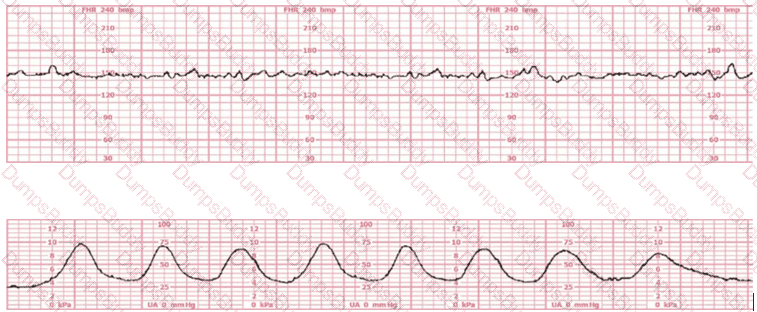

A woman (G1P0) arrives in triage with a pain score of 4/10 at 39-weeks gestation. The fetal heart rate tracing shown is obtained. The best intervention is to: